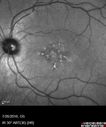

pattern_brcl_072616_04.png

Pattern Dystrophy - Probably Early Butterfly426 views33 year old with normal vision and no visual complaints - normal color vision00000

(0 votes)